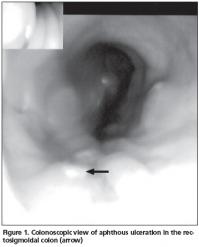

46 year-old patient with rheumatoid arthritis presented with severe diarrhea causing a weight loss of 5 kg. She has been followed-up at rheumatology out-patient clinic for 14 years. She was started on methotrexate 15mg/week/i.m 5 years ago. 30 months ago leflunomide 20mg/day was added to her treatment for continuing disease activity. Four weeks before presentation she started having diarrhea. She had no history of fever or night sweats. Her stool analysis did not reveal any infective agent including bacteria and parasitic microorganisms including Entamoeba histolytica, Giardia lamblia. Gastroscopic and colonoscopic examination showed pangastritis with mucosal hyperemia and multiple colonic aphthous ulcerations (Figure 1). Pathological examination revealed focal ulceration, cryptitis, mixed inflammation at the lamina propria. However, crypt abscess, crypt distortion, granulomas and amebic organisms were not seen. In view of these findings diagnosis of drug induced colitis was made and leflunomide was stopped. Three weeks later, diarrhea was resolved.

The major type of diarrhea associated with leflunomide is acute diarrhea, which usually appears during the first few weeks of treatment and usually transient or responds to a decrease in the dose of leflunomide[11]. There is no information about the mechanism of acute diarrhea induced by leflunomide. To the best of our knowledge, two cases were reported previously with severe chronic diarrhea, lasting more than one month and appearing long time after the start of leflunomide therapy[12]. One case had developed ulcerative and haemorrhagic colitis eighteen months after starting leflunomide treatment and the other case had developed microscopic colitis two years after starting treatment. Both cases had shown clinical improvements after stopping leflunomide treatment[12]. In addition to these findings our case had aphthous ulcerative colitis.